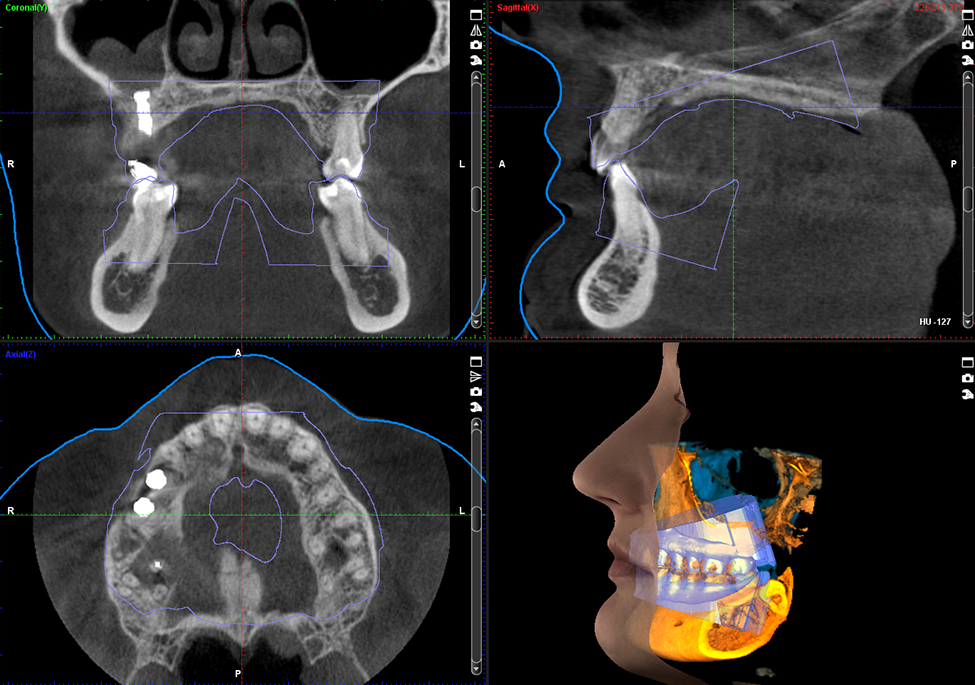

Obrazy Kliniczne Planmeca ProMax 3D Mid